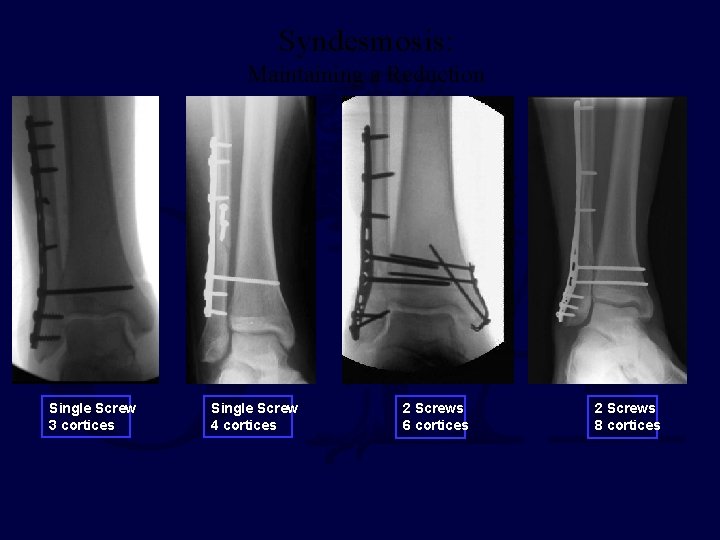

Syndesmosis: Maintaining a Reduction Single Screw 3 cortices Single Screw 4 cortices 2 Screws 6 cortices 2 Screws 8 cortices

Syndesmosis: Maintaining a Reduction 3. 5 mm vs 4. 5 mm screw(s) 3 cortices vs 4 cortices Retain vs Removal Metallic vs Bioabsorbable NO CONSENSUS